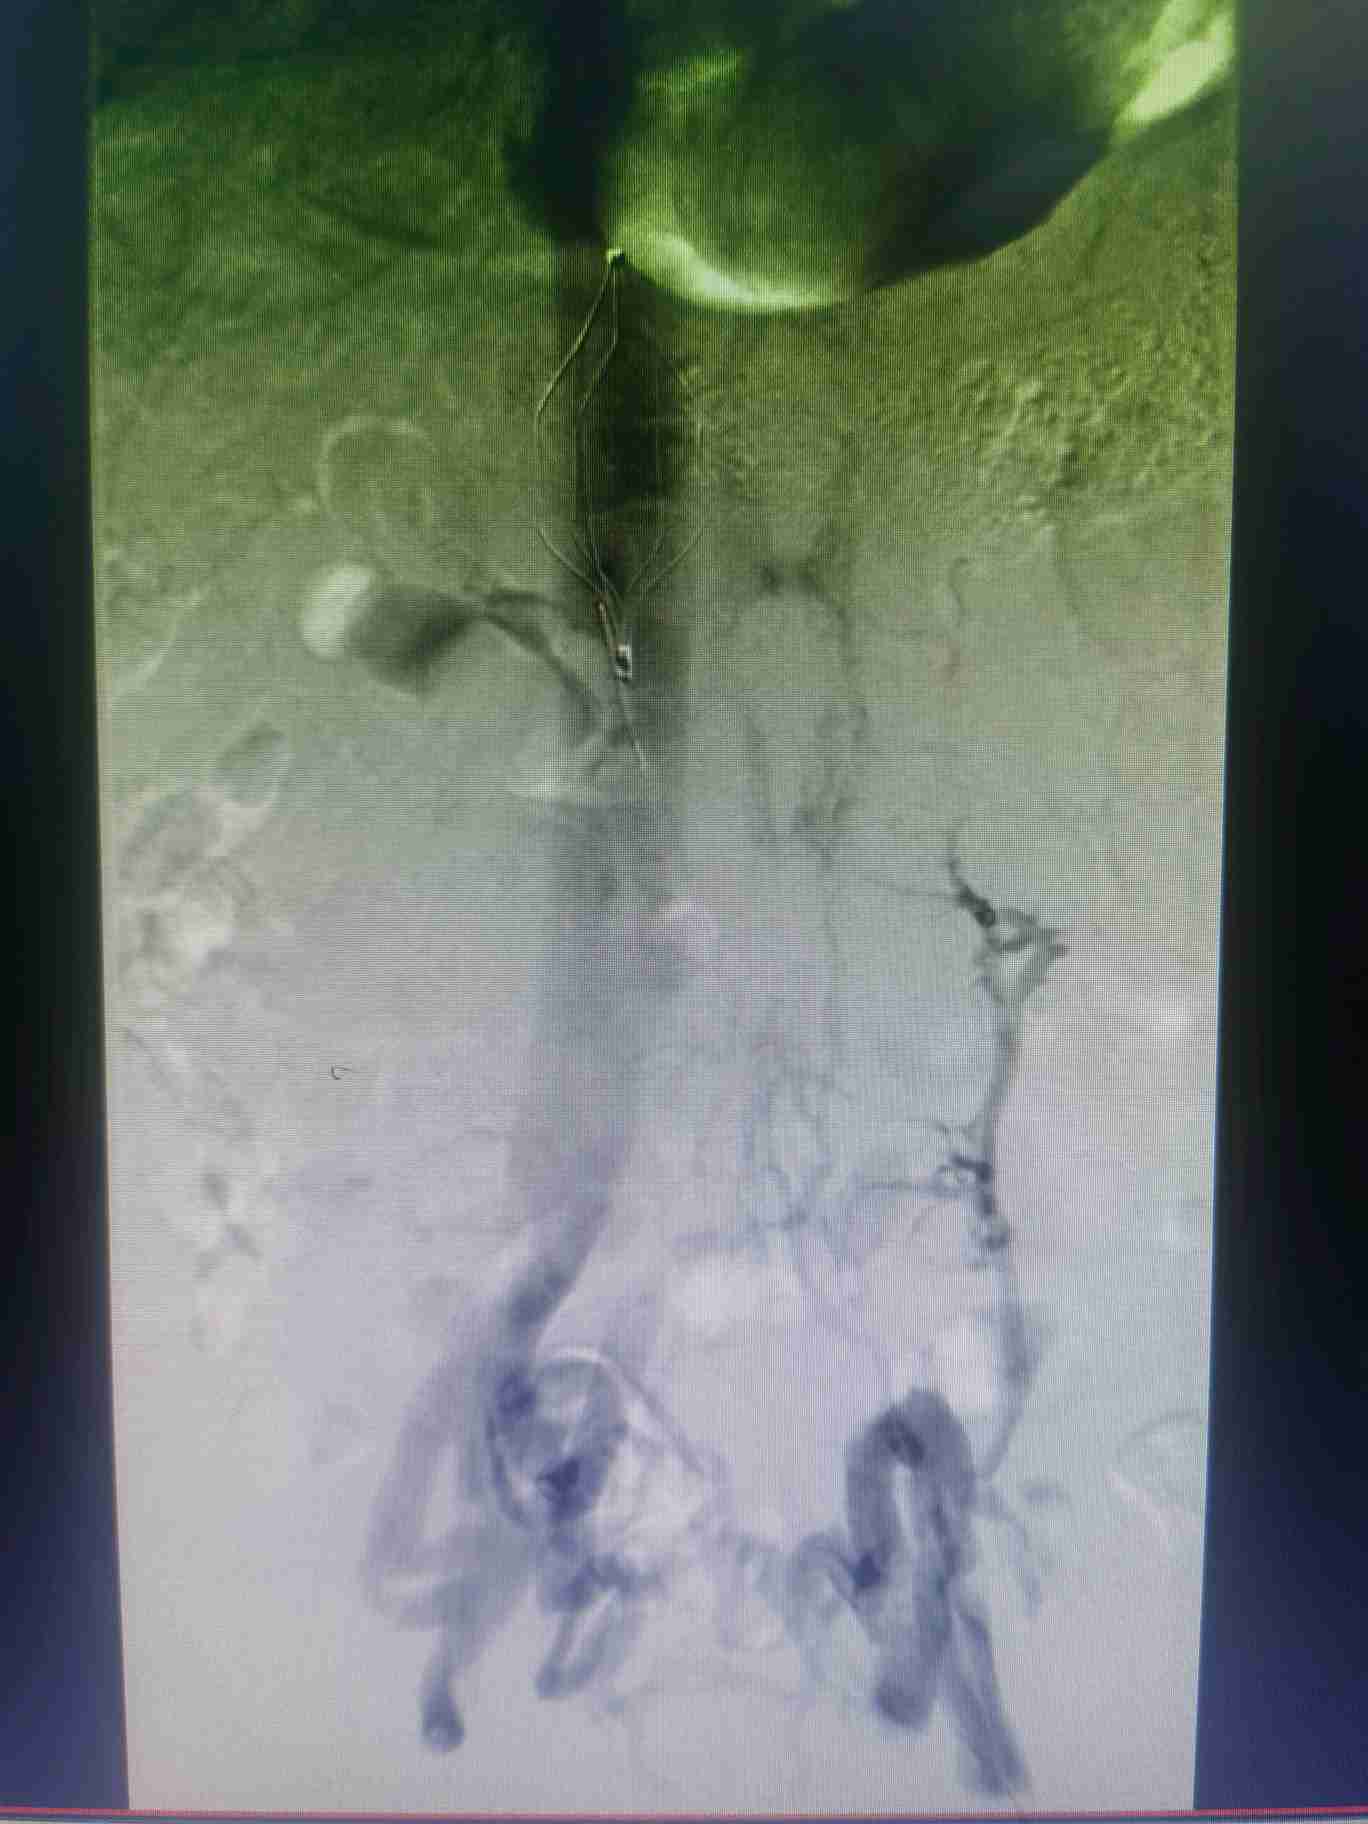

答:首先需要做的就是看医生;然后避免挤压、按摩、揉搓患肢,可用专科垫枕抬高患肢。主要治疗方式为:抗凝、溶栓、外科手术、介入手术等。

答:这个就需要根据患者自身情况制定个性化治疗策略,主要策略为:①保守抗凝治疗:②系统溶栓治疗;③导管接触性溶栓治疗;④机械性血栓清除治疗;⑤必要时球囊扩张和支架植入治疗;⑥急危重症病人需切开取栓治疗等。